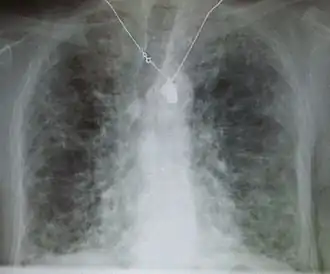

Pneumocystis pneumonia can present with interstitial lung disease, as seen in the reticular markings on this AP chest x-ray.

A chest X-ray demonstrating pulmonary fibrosis due to amiodarone